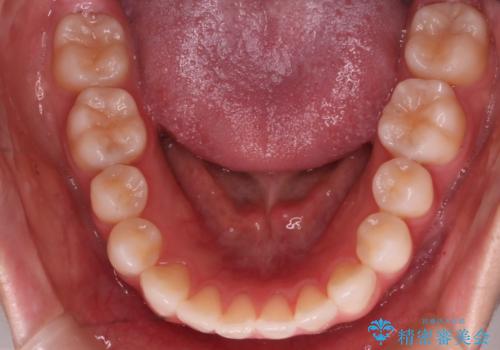

- 前歯の捻転とかみ合わせを主訴に来院されました。今回は抜歯をせずにIPRを実施し、並べる計画を立てました。

ワイヤー矯正を行いながら、顎間ゴムを患者さまにご協力していただき、短い期間で終了できました。